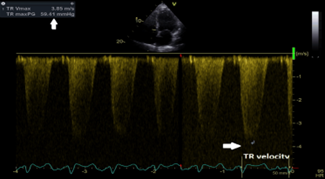

Continuous wave (CW) Doppler interrogation of the tricuspid regurgitant jet yielded a jet velocity at 3.85 m/sec allowing calculation of systolic pulmonary artery pressure( SPAP) at 67 mmHg with estimated right atrial pressure at 8 mmHg (Figure 6); the inferior vena cava was normal in size at 1.6 cm and collapsing normally with inspiration.

Figure 6: CW Doppler interrogation of the tricuspid regurgitant jet yielded a jet velocity at 3.85 m/sec (white arrows) allowing calculation of SPAP at 67 mmHg with estimated right atrial pressure at 8 mmHg; the inferior vena cava was normal in size at 1.6 cm and collapsing normally with inspiration.

CW=continuous wave Doppler; m/s=meter/second; SPAP=systolic pulmonary artery pressure.